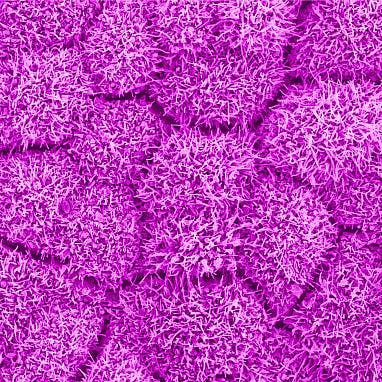

Tam’s latest work targets the retinal pigment epithelium (RPE), a layer of tissue behind the light-sensing retina that supports the metabolically active retinal neurons, including the photoreceptors. The retina lines the back of the eye and captures, processes, and converts the light that enters the front of the eye into signals that it then transmits through the optic nerve to the brain. Scientists are interested in the RPE because many diseases of the retina occur when the RPE breaks down.

Tam and his team developed a novel AI-based method called parallel discriminator generative adverbial network (P-GAN)—a deep learning algorithm. By feeding the P-GAN network nearly 6,000 manually analyzed AO-OCT-acquired images of human RPE, each paired with its corresponding speckled original, the team trained the network to identify and recover speckle-obscured cellular features.

When tested on new images, P-GAN successfully de-speckled the RPE images, recovering cellular details. With one image capture, it generated results comparable to the manual method, which required the acquisition and averaging of 120 images. With a variety of objective performance metrics that assess things like cell shape and structure, P-GAN outperformed other AI techniques.